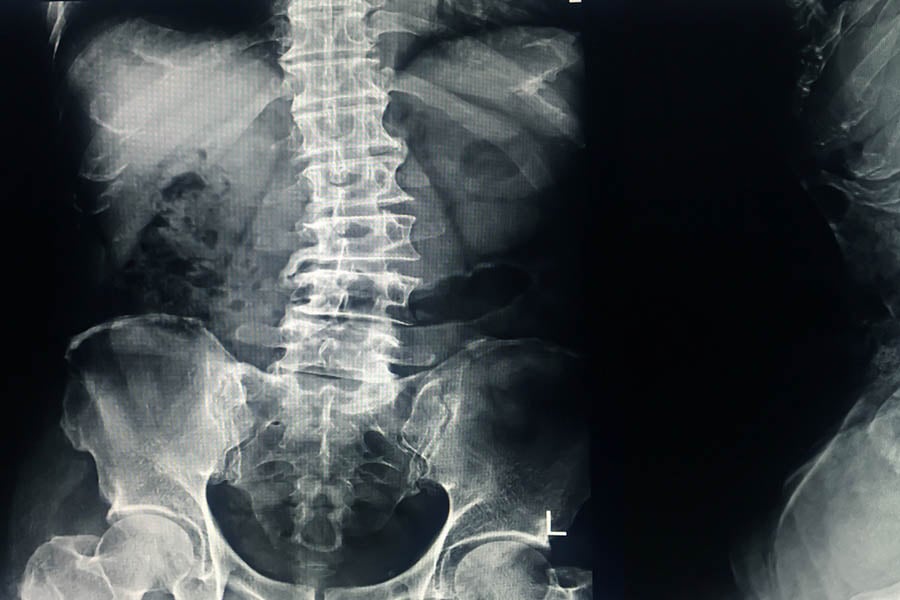

Деформации на гръбначния стълб (сколиоза или други аномалии)

Спина бифида често води до деформация на гръбначния стълб, като сколиоза (странично изкривяване на гръбначния стълб). Това се случва, защото недоразвитите мускули и нерви не поддържат правилно стойката на гръбначния стълб.

Освен сколиоза, могат да се наблюдават и други аномалии като кифоза (изкривяване на гръбначния стълб към гърба) и лордоза (изкривяване напред в долната част на гръбначния стълб). Тези деформации могат да причинят болка и допълнителни трудности в движението.

Диагнозата може да се постави и след раждането чрез рентгенови снимки, компютърна томография (CT) или магнитен резонанс (MRI), които дават детайлна информация за състоянието на гръбначния стълб и нервната система.